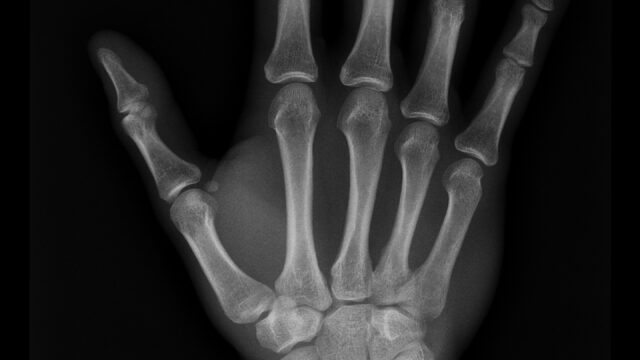

১। এক্স-রেঃ আধুনিক চিকিৎসা বিজ্ঞানের কথা বলতে গেলে এক্সরের কথা আপনা-আপনি চলে আসে যা না বললেই নয়। চিকিৎসা বিজ্ঞানের ভূমিকার কথা বলতে গেলে এক্সরে একটি অসামান্য অবদান। এই এক্সরে মেশিন আবিষ্কার করেন বিজ্ঞানী উইলহেম কনার্ড রন্টজেন ১৮৯৫ সালে। রন্জনরশ্নির আরেক নাম এক্সরে। প্লেন এক্সরে থেকে শুরু করে কন্ট্রাস্ট এক্সরে, সিটি স্ক্যান(PLAIN CT, CONTRAST CT, SPIRAL CT. 3-D CT RECONSTRUCTION, ULTRAFAST CT) পিইটি সিটি সহ আরো অনেক ক্ষেত্রে এক্সরের ব্যবহার দিনদিন বেড়েই চলেছে।

আমাদের দৈনন্দিন জীবনে এক্সরে মেশিনের বিকল্প নেই। আমাদের শরীরের যেকোন জায়গা ভেঙ্গে গেলে বা যেকোন ধরনের সমস্যা দেখা দিলে তা আমরা বাইরে থেকে দেখতে চাইলে আমাদেরকে এক্সরে মেশিনের মাধ্যমে এক্সরে করতে হবে।

অতএব, আমরা বুঝতে পেরেছি নিশ্চয় আধুনিক চিকিৎসা ক্ষেত্রে বিজ্ঞানের ভূমিকায় এক্সরে একটি অকল্পনীয় আবিষ্কার।